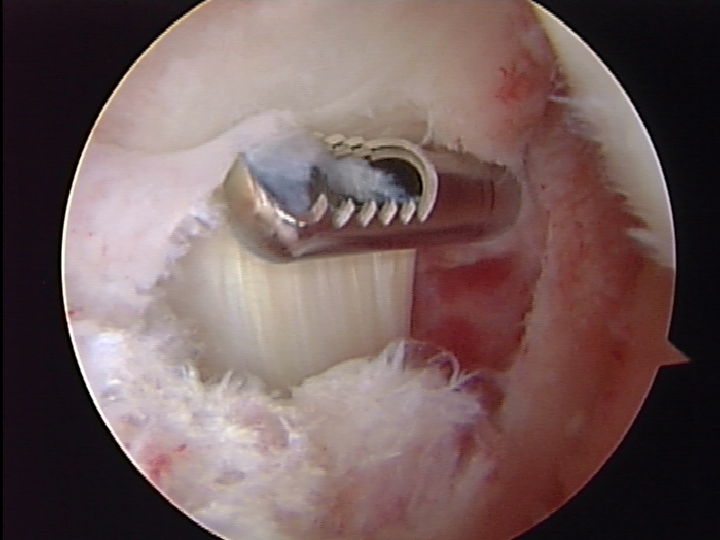

Pictures 5-6 demonstrate the drilling of the tibial tunnel and passing the graft. Great care is taken to visualize and protect the vascular and neurological structures in the back of the knee. In most patients the neurovascular structures are within 3-5 mm of the tibial tunnel

Picture 7-8 demonstrate the drilling of the femoral tunnel